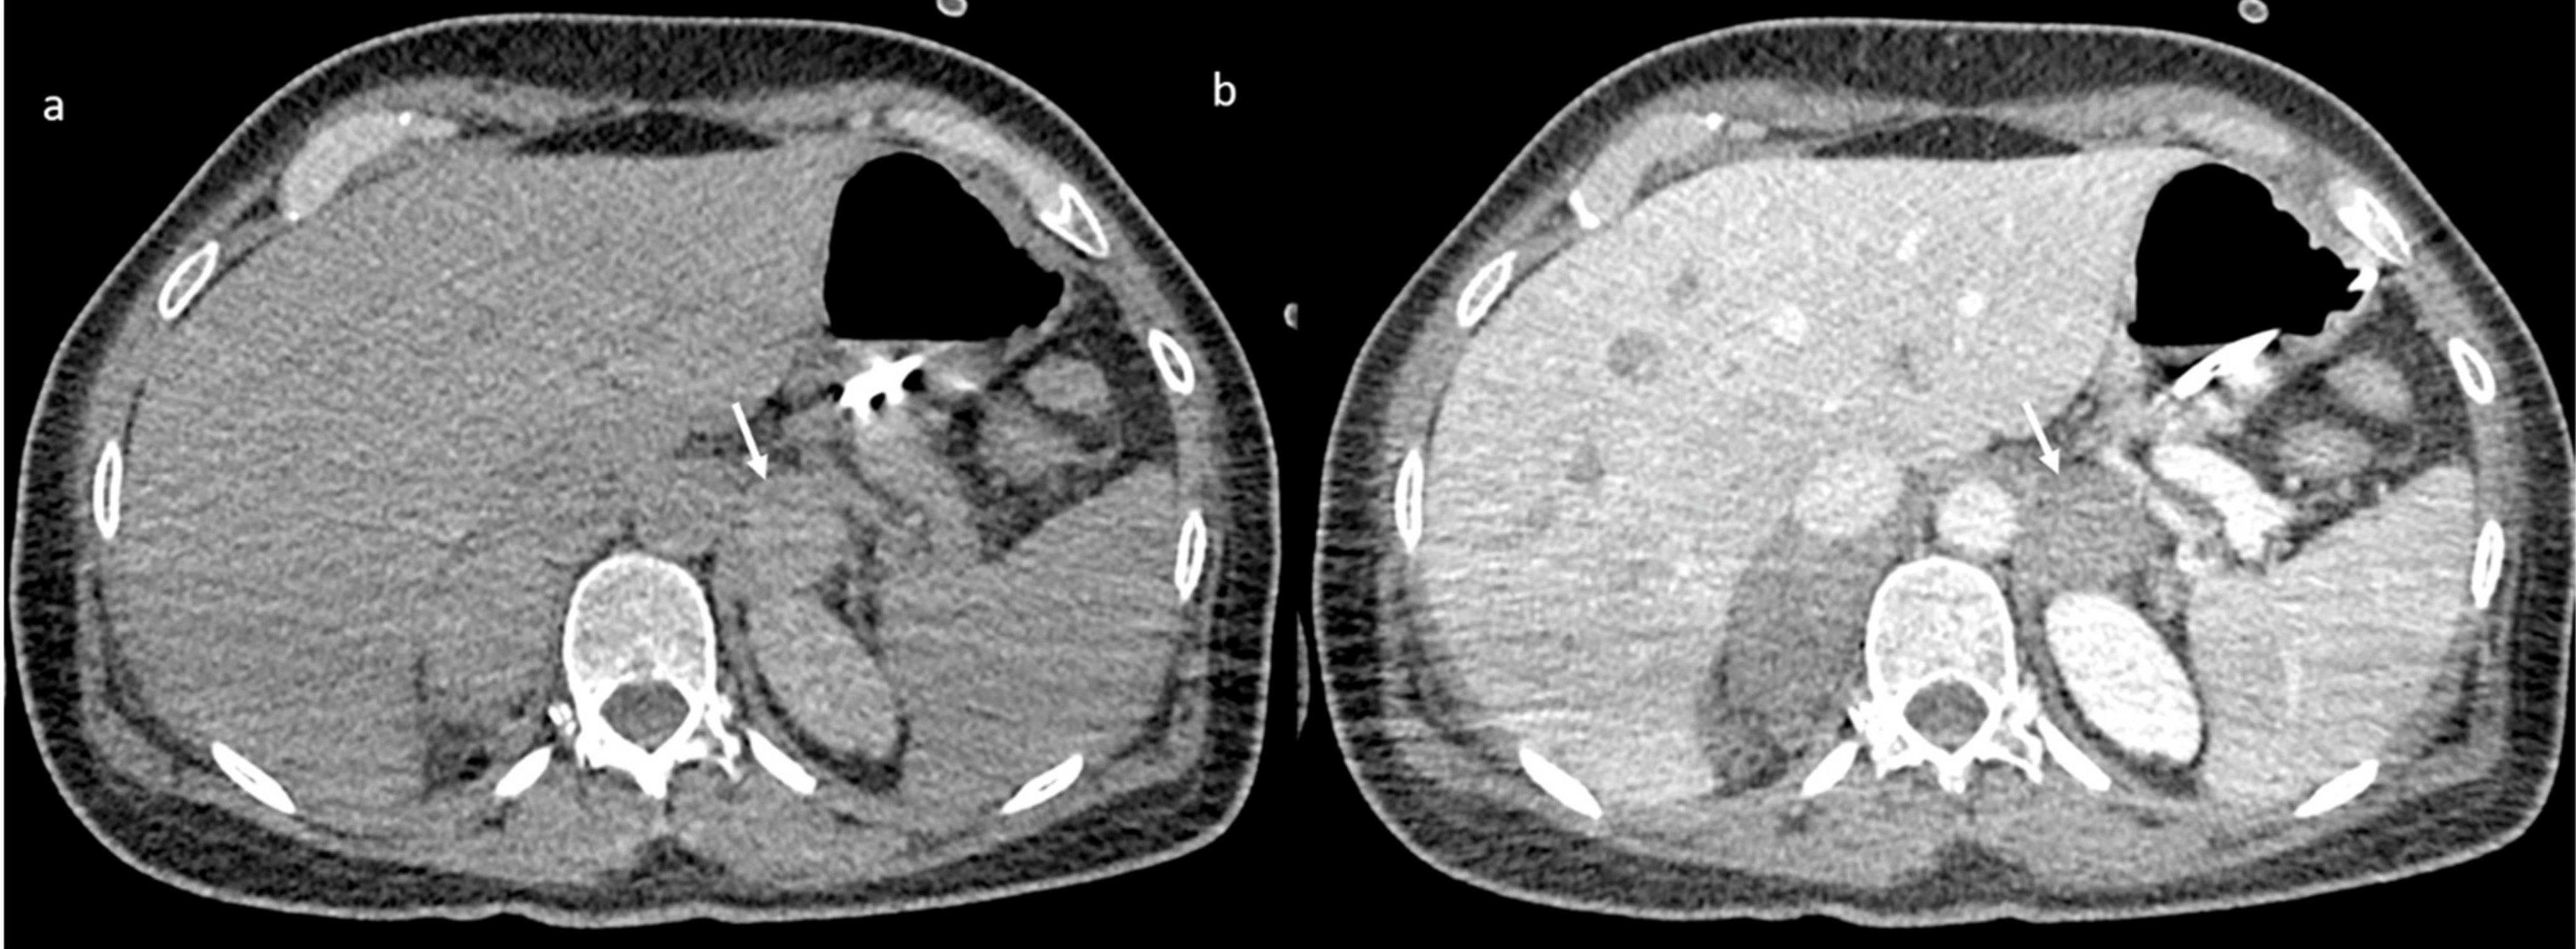

An abdomen angio-CT showed filling defects at the level of left portal branch (Figure 7) and at the level of right suprahepatic vein (7). Bilaterally, it was adrenal hemorrhage (Figure 8) and blood in the pelvis.

Figure 8.

CT scan without (a) and with contrast (b) shows adrenal hemorrhage (arrow).